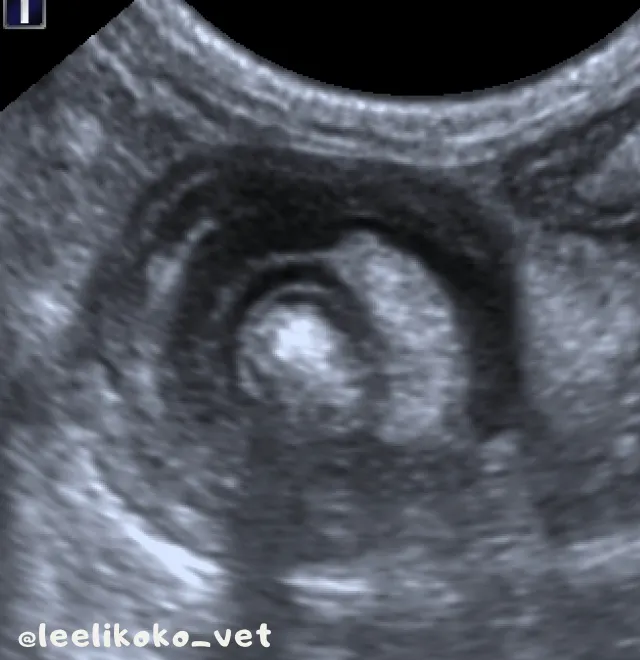

- 橫切面可見同心圓樣的靶狀影像

腹腔超音波- 腸套疊位置橫切面